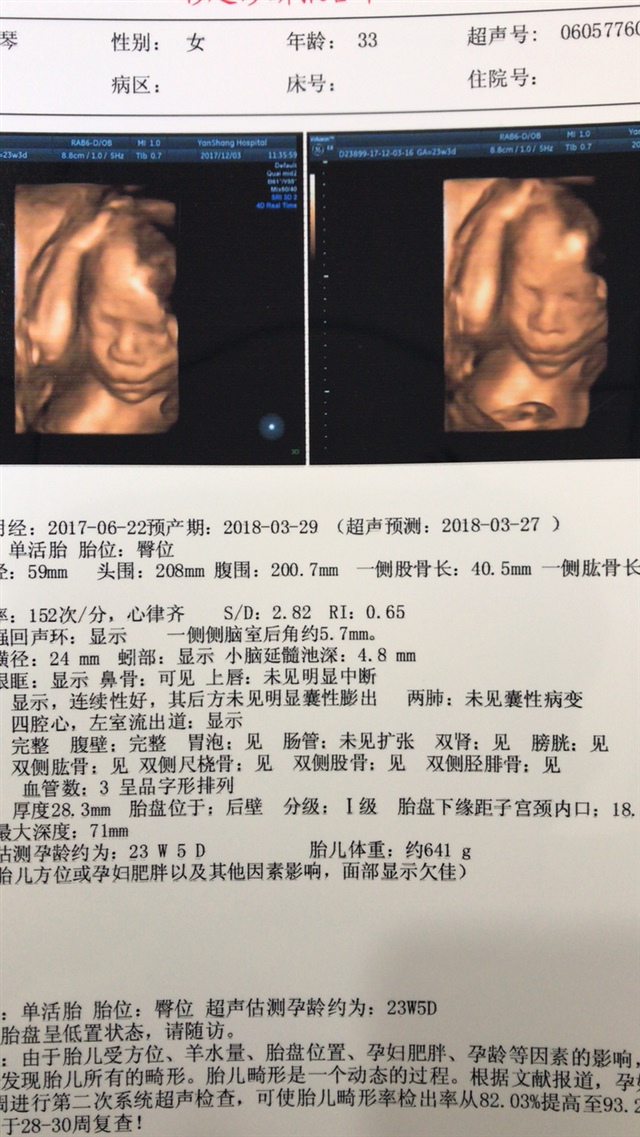

四维和三维有啥区别啊

等等我[帖主]:我也不太懂,好像是四维彩超更立体画面更清晰,宝宝的五官和内在发育情况看得更清楚一些。